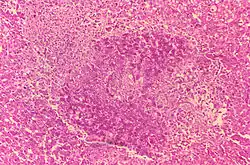

- Histologic evidence of granulomatous hepatitis on hepatic biopsy

- Radiologic alterations in infected vertebrae: the Pedro Pons sign (preferential erosion of the anterosuperior corner of lumbar vertebrae) and marked osteophytosis are suspicious of brucellic spondylitis.